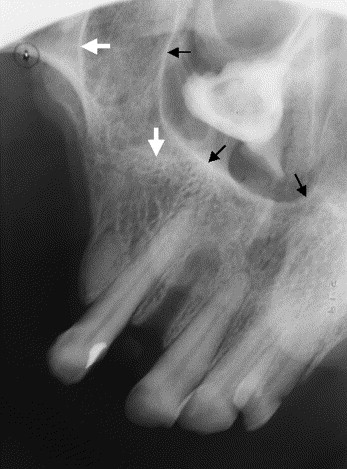

2. What condition can be seen in the following X ray? ( Open arrow)